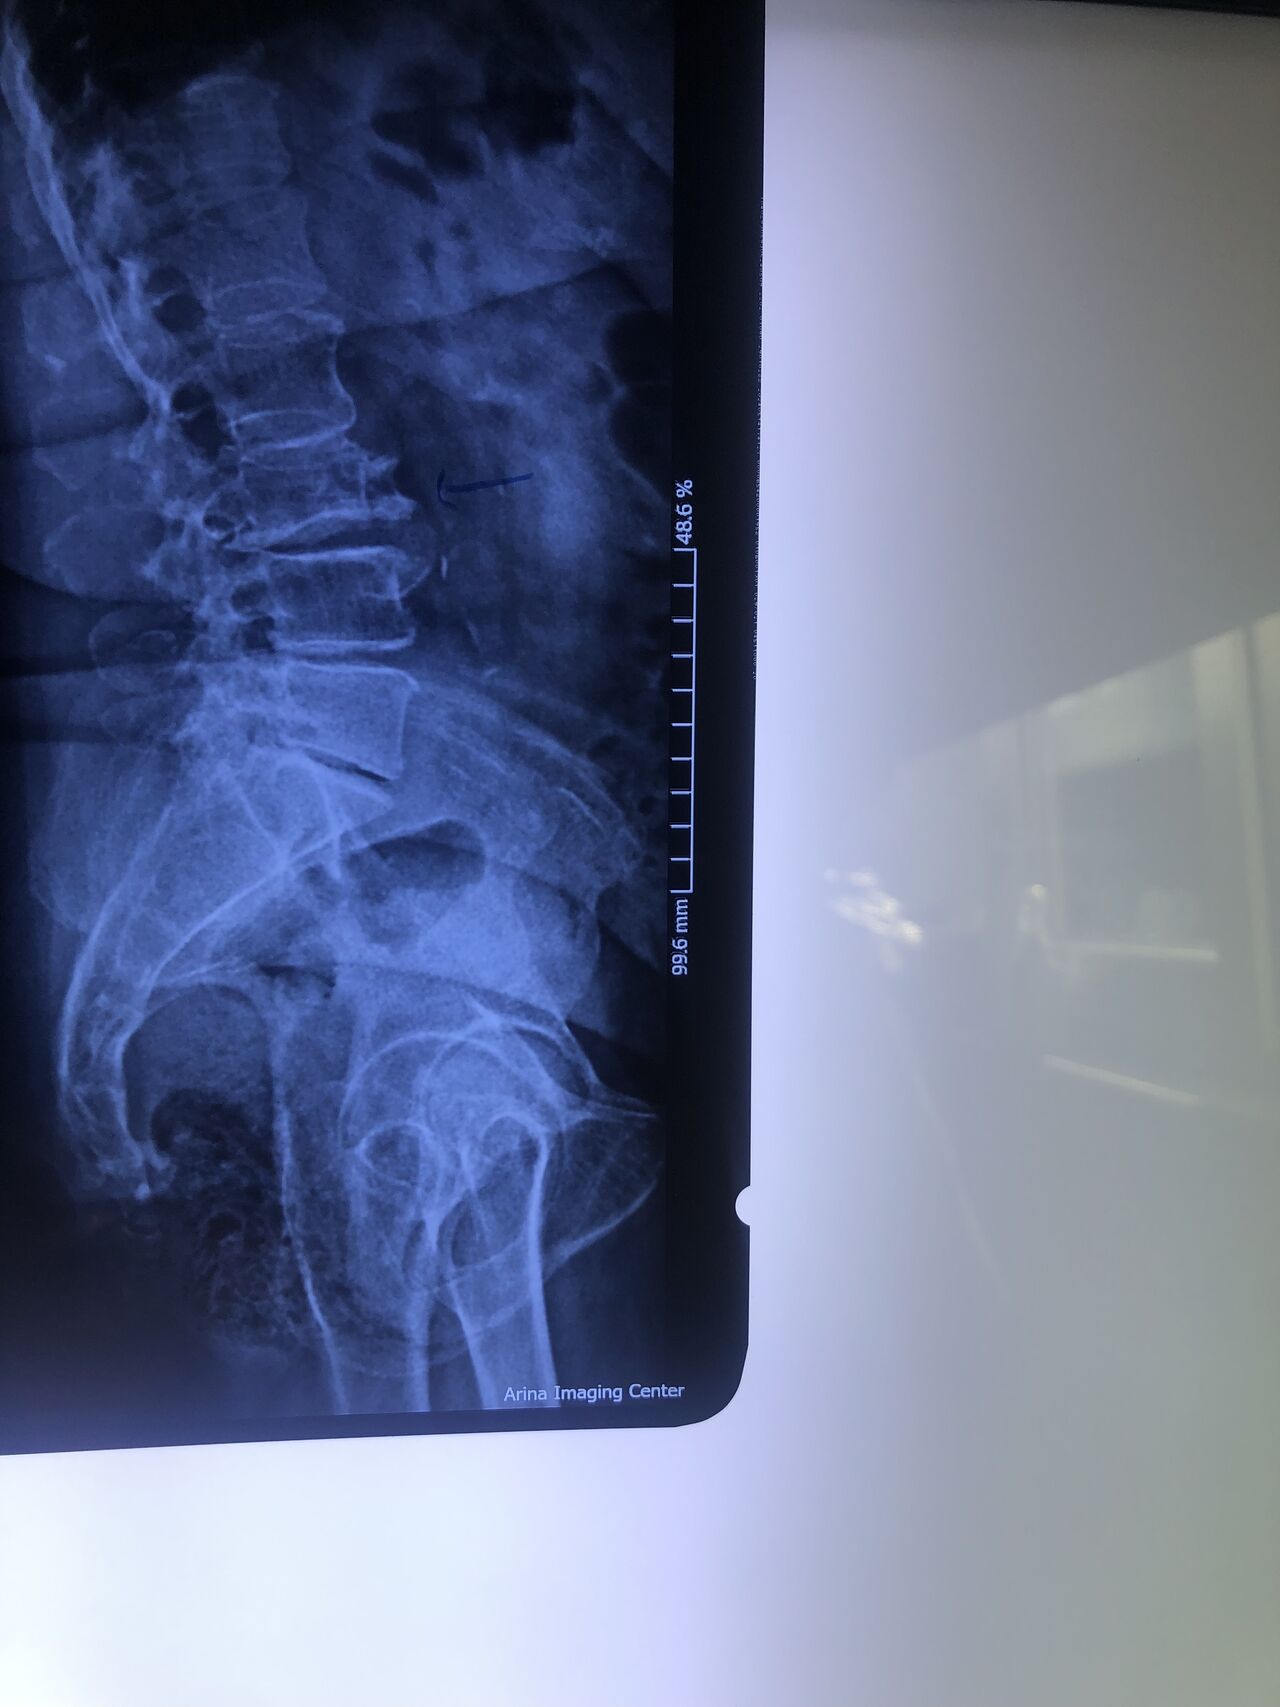

Since I’ve noticed instability in some segments I asked for dynamic L/S x ray:we see mild L4 ant listens due to DjD/DDD. There is not any pars defect.

This time presented to my cl with LBP mainly during sleep at night. Just brought me her mri. According to her mri I ordered dynamic L/S X. R.

Is ant listhesis of L4 unstable or stable?

From several compression fractures we see which of is acute/ subacute and which ones are chronic fx?